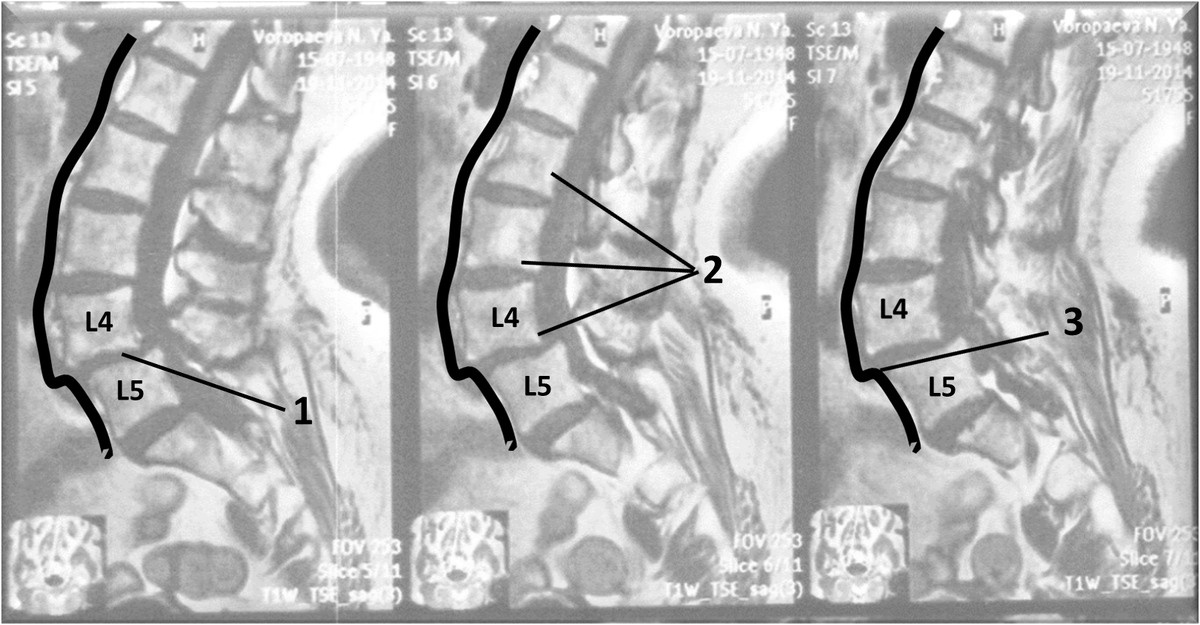

Снимок позвоночника с передним спондилолистезом ("антелистезом") прорисовка. собственные наблюдения автора

1. Межпозвонковый сегмент L4-L5 со спондилолистезом и сопутствующими межпозвонковыми грыжами; 2. Тела позвонков выше сегмента L4-L5, значительно смещены вперед по отношению к телу позвонка L5; 3. Линия, контурно огибающая переднюю поверхность позвоночника, имеющая форму «ступеньки» на уровне сегмента L4-L5.